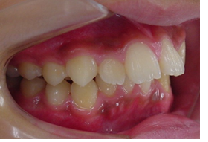

当矯正歯科医院ではMEAW法(マルチループ)で治療する事で非抜歯で治療しています。

MEAW法(マルチループ)を利用することで以下の様に上顎前突が改善されていきます。

初診時

治療途中

終了時